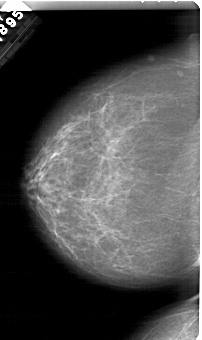

A_2001_1.LEFT_CC

LEFT_CC LINES 6106 PIXELS_PER_LINE 3631 BITS_PER_PIXEL 12 RESOLUTION 43.5 NON_OVERLAY